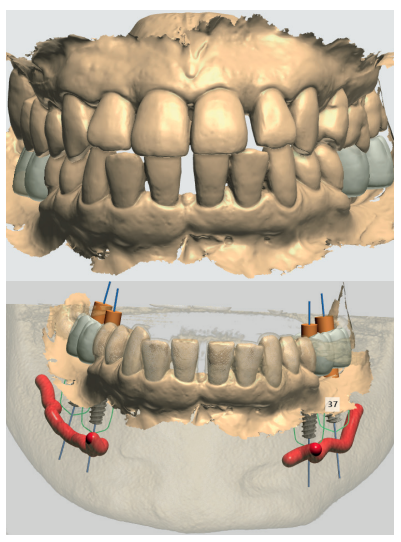

Caso clínico: Se presenta el caso clínico de una paciente con hipertensión, diabetes tipo II, hipotiroidismo, depresión, obesidad y déficit de vitamina D. Se hace una revisión de la actuación del odontólogo en la clínica cuando se presentan pacientes con dichos cuadros y las consideraciones a tener en cuenta con respecto a la prescripción y administración de medicación. El objetivo es presentar recomendaciones de tratamiento a partir de un caso clínico de una paciente con varias afecciones sistémicas en la que se realiza un tratamiento multidisciplinar. Para eso se ha realizado una revisión narrativa que se considera útil para la actividad clínica diaria

Clinical case: The clinical case of a patient with hypertension, type II diabetes, hypothyroidism, depression, obesity and vit D deficiency is presented. A review is made of the performance of the dentist in the clinic when patients with these conditions appear and the considerations to take into account with respect to the prescription and administration of medication. The objective is to present treatment recommendations based on a clinical case of a patient with several systemic conditions in which a multidisciplinary treatment is carried out. For this, a narrative review has been carried out that is considered useful for daily clinical activity.